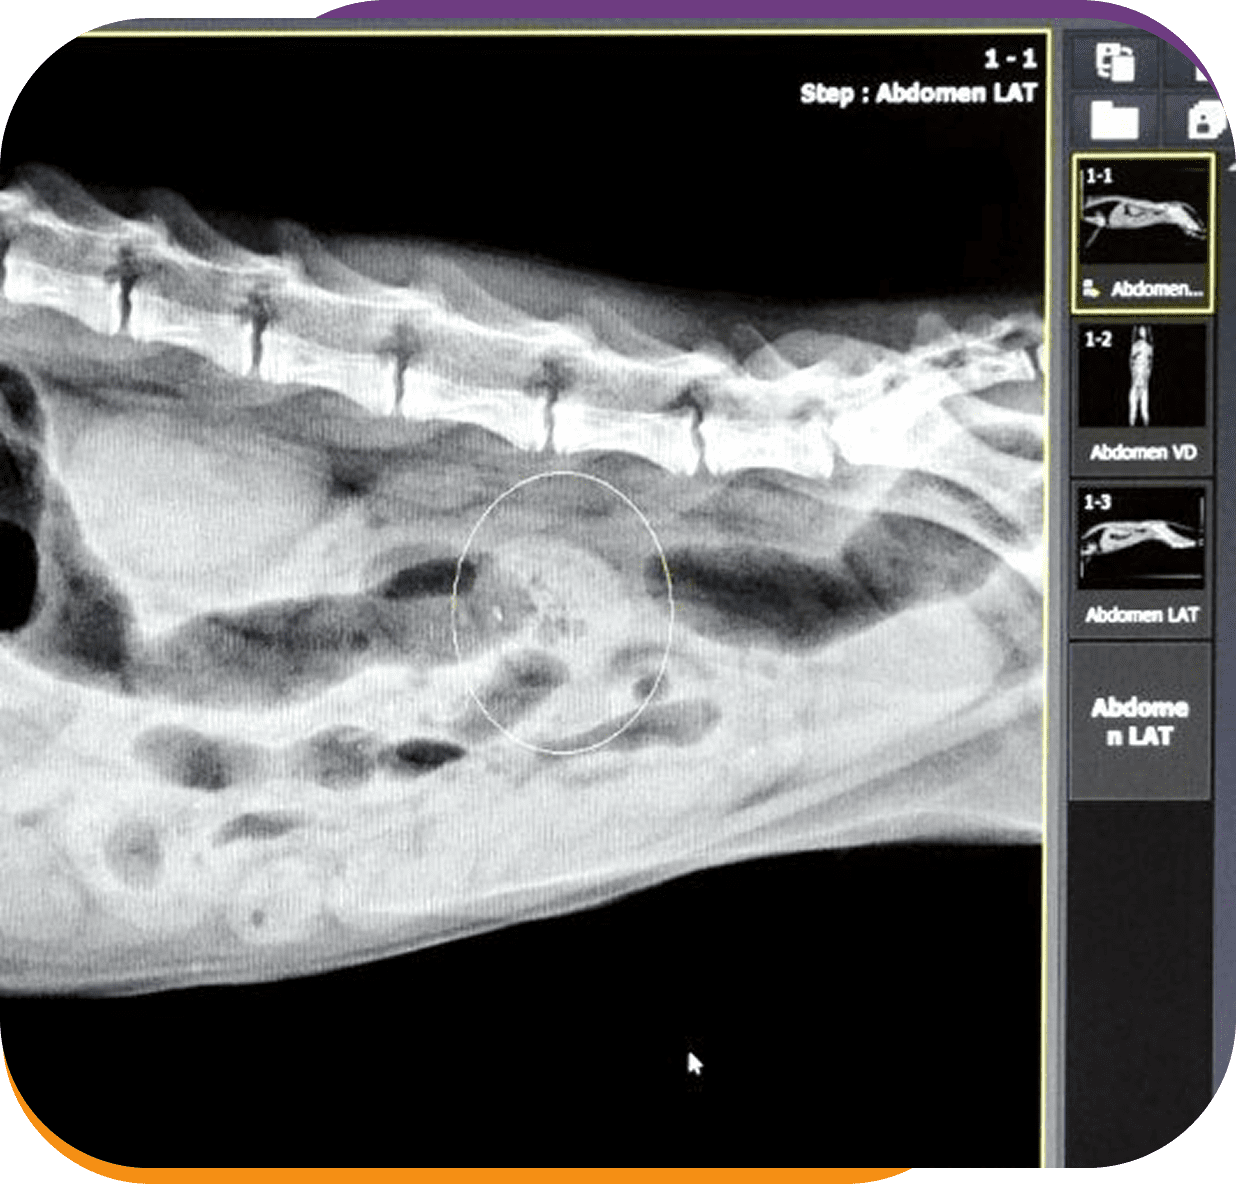

Animal abdominal X-ray image